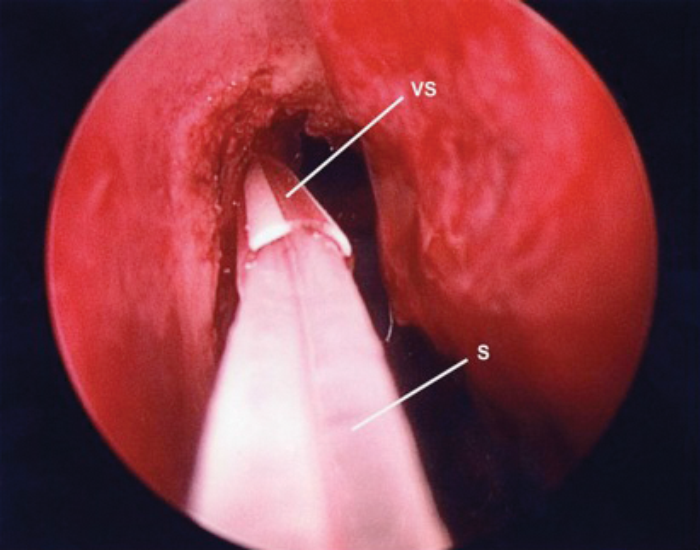

A wide nasolacrimal window is created. Silastic lacrimal stents are then placed via both upper and lower canaliculi, retrieved endonasally (Figures 7a & b) and tightened over a 18 gauge venflon sheath / silastic tubing (Figure 8) to prevent upward migration of the stent knot. The stent loop is ensured not to be too tight as it may cheese wire through the puncta. We prefer using ligaclips to stabilise the stents (Figures 9a & b) in place of knots to avoid any risk of slippage of the knot leading to stent laxity. The nasal mucosa is trimmed and folded back to cover the exposed bone and haemostasis achieved with suction diathermy.

VS - Venflon Sheath S - Stent

Figure 8. Silastic stents guided through trimmed venflon sheath.